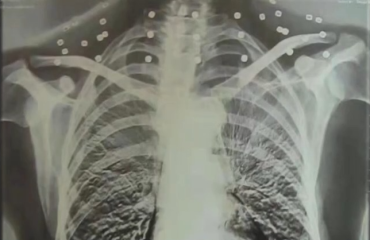

手术做了六个小时。医生说,刀锋离颈动脉只差毫厘,是真正的生死一线。